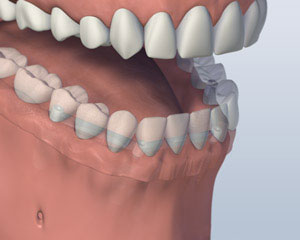

酒吧附着体义齿

另一种选择涉及将四到六种植体, 这取决于你的下巴大小或形状, 进入你的下颚. 后完全愈合, 植入物与一个特制的支撑杆连接. 你的假牙将与附着到支撑条特殊的内部固定夹进行, 使假牙牢固卡入到位. 这就是所谓的 “覆盖义齿.” 这个方案的优点是,它更稳定比第一个选项,允许非常小的义齿运动. 你的义齿仍然是可拆卸,便于清洁和维护.

1. 之前

2. 植入放置

3. 义齿附